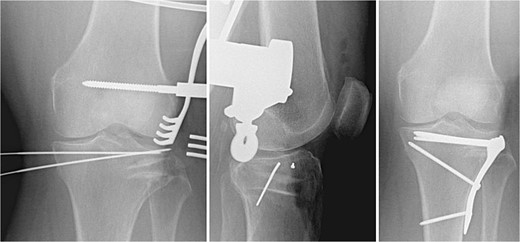

The void left in the lateral tibial condyle after elevation of the articular surface is usually triangular in shape. The depth and lateral height are measured. A tricortical iliac crest allograft is selected and cut to an appropriate size based on these measurements. The allograft is then inserted parallel to the joint surface to raft the articular surface. They usually fit nicely thanks to the natural triangular shape of the allograft (Fig. 2).

Tricortical iliac crest allograft preparation, measurement, cut to an appropriate size, and insertion into the defect.